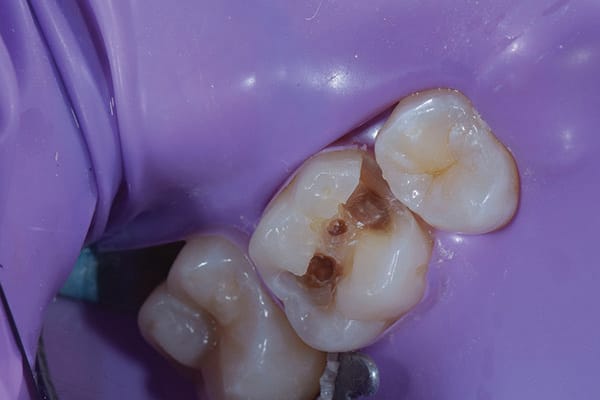

Once the operative field was isolated, a No. 557 carbide bur was used in a high-speed handpiece to efficiently remove the existing composite restoration and extend the preparation mesially. The Class II preparation was then refined using a fine diamond chamfer bur. Initial caries removal was performed using a round carbide bur in a slow-speed attachment (Figure 2). After initial caries removal, a caries indicating solution (Seek™ Caries Indicator, Ultradent) was used to stain any suspected remaining caries (Figure 3).4 Caries indicating solutions target demineralized dentin with a highly visible stain, providing an efficient and effective means of ensuring that only the infected dentin is subsequently removed, leaving the affected dentin behind (Figure 4).